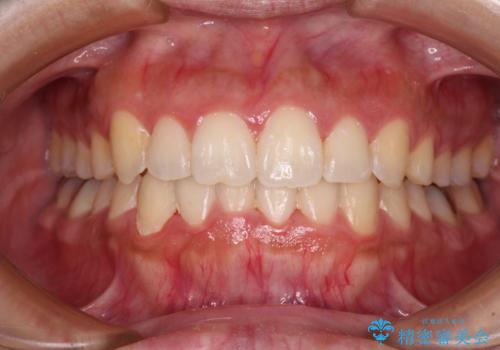

- 口元の突出感と口の閉じにくさを気にして来院された患者様です。

上下左右第一小臼歯4本を抜歯し、ワイヤー装置にて口元を引っ込めるよう矯正治療を行うこととしました。

2年~2年半が治療期間の目安でしたが、順調に治療が進み、1年9か月で満足のいく歯列となりました。